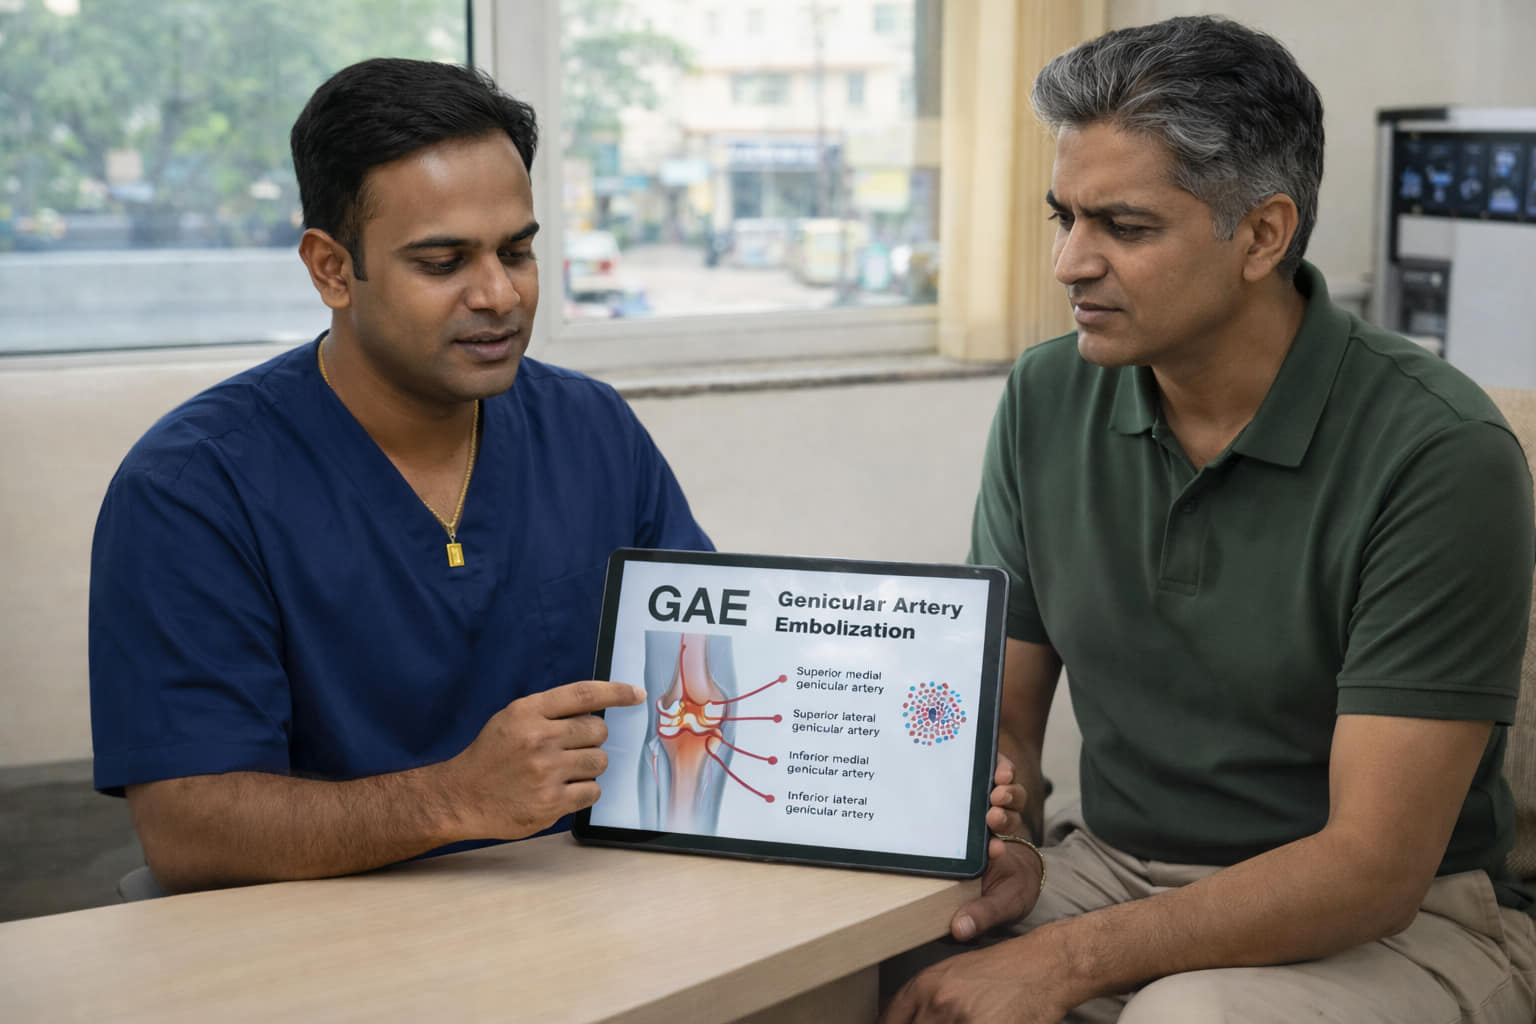

GAE is a novel, image-guided treatment developed to relieve chronic knee pain by blocking abnormal blood vessels in the joint. The procedure involves injecting tiny embolic agents—such as particles or coils—into specific genicular arteries, thereby reducing excess blood flow that fuels inflammation and pain.

In osteoarthritic joints, abnormal neovascularization—the formation of new, fragile blood vessels—plays a key role in inflammation and pain. GAE targets these vessels with precision:

- Step 1: Under angiographic guidance, the interventional radiologist maps the network of genicular arteries that supply the inflamed joint.

- Step 2: Embolic materials are introduced to selectively block these vessels.

- Step 3: Blood flow to the painful areas is reduced, leading to less inflammation and pain.

Why Anatomy Matters

Success depends heavily on the operator’s detailed knowledge of genicular artery anatomy, including its variations. Accurate targeting helps maximize efficacy and minimize risks like non-target embolization.